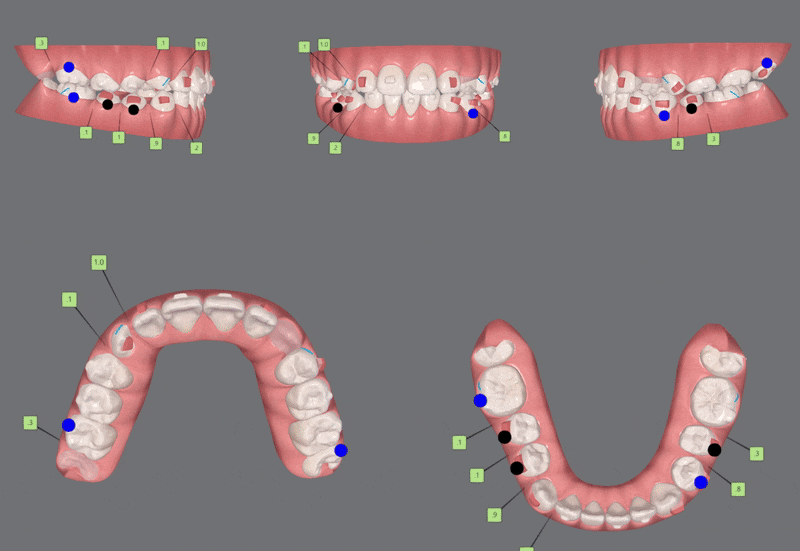

3rd(17개)

세번째는 17개의 장치로

이전의 클린체크를 이전의 클린체크를

상호 보완, 개선 하여 마무리 해드렸습니다.

4th (22개)

마지막으로 섬세한 디테일링을 위해

네번째 클린체크

(총 22개의 장치)를 진행해드렸습니다.